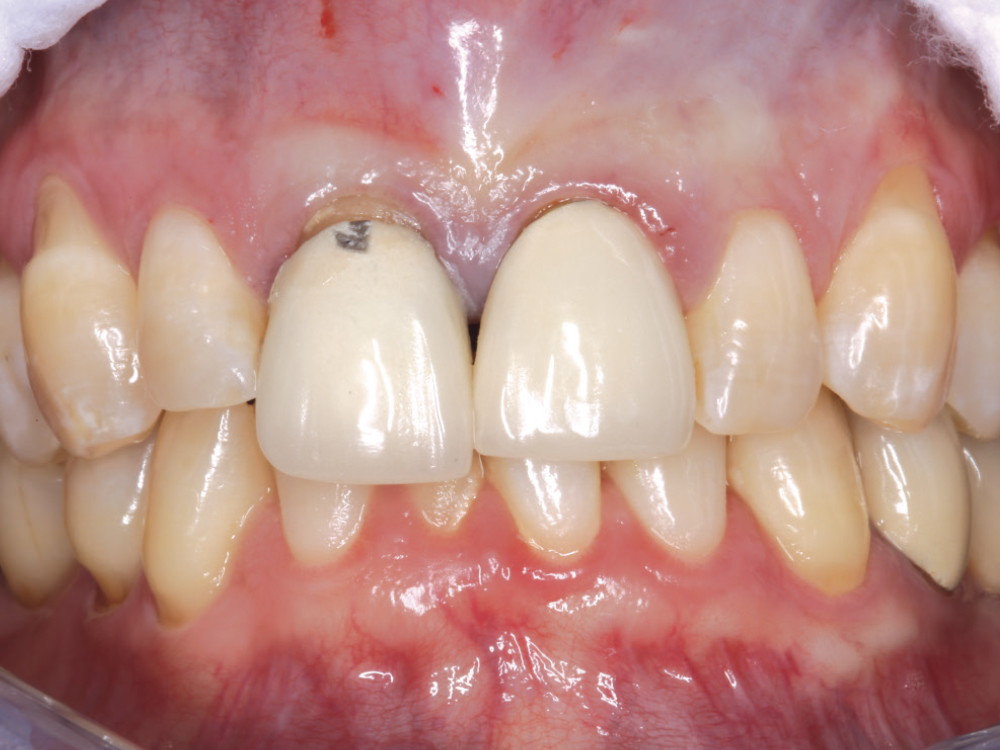

Life-like esthetic restorations

Scanner view of abutments

Four months after the surgical procedure, gold-tone custom abutments and all-ceramic crowns were delivered. The custom abutments and implant crowns were produced for a reduced fee because of the 20% discount offered by Glidewell for restorations over Hahn implants. The final restorations achieved esthetic, lifelike emergence profiles due to the soft-tissue management provided by the immediate provisional restorations during the healing phase. Note the crestal bone levels around the Hahn implants.